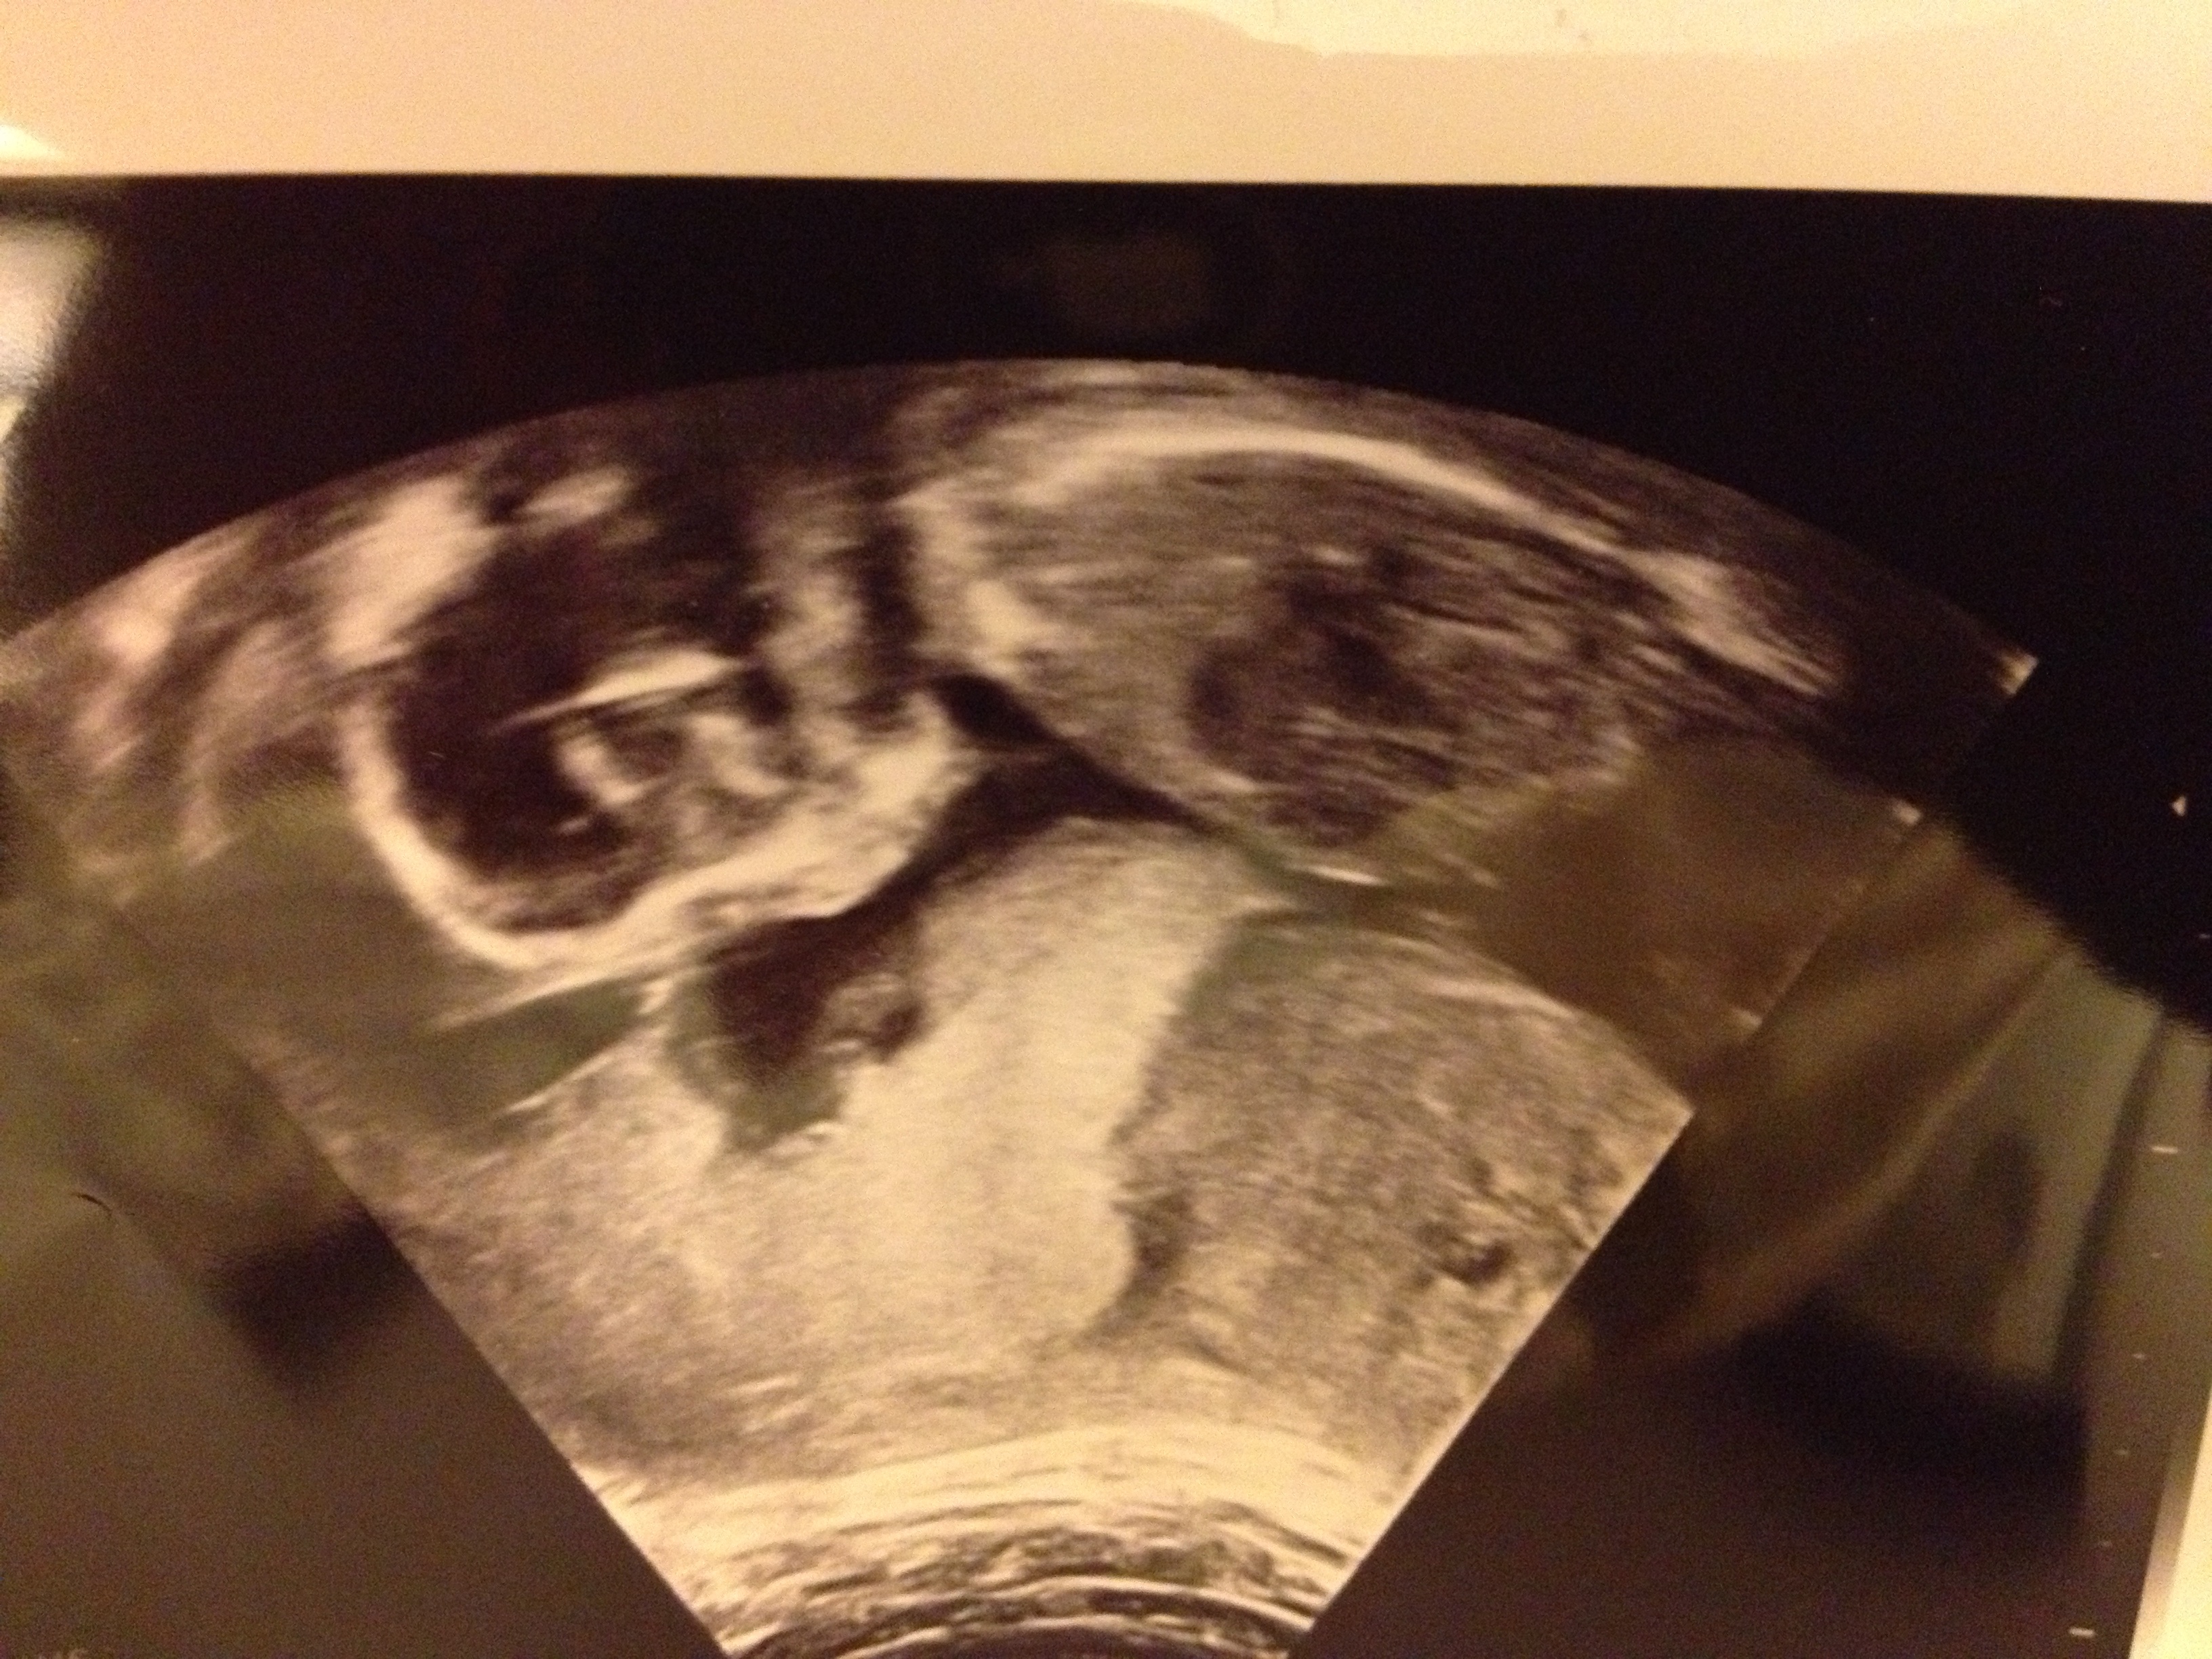

Attachment 15878

12 wks 2 days